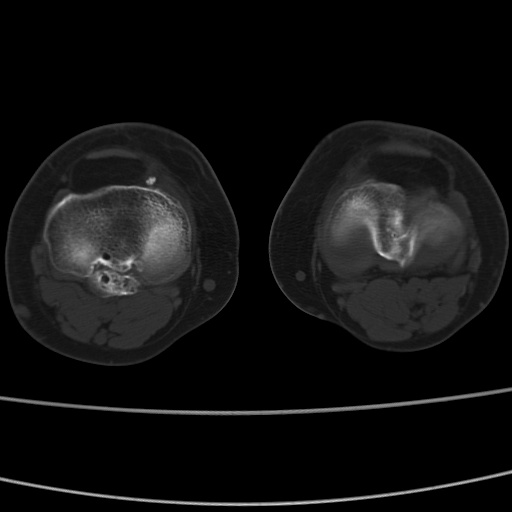

女性,50岁。【请提供患者临床症状体征】

右膝关节退行性改变,关节游离鼠。

右膝关节退行性改变,滑膜黏液囊钙/骨化并游离。